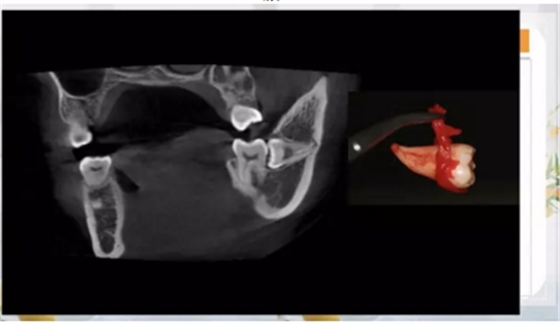

如何才能完整而且沒(méi)有骨損傷的拔掉這顆牙齒呢?

那就兩個(gè)一起拔!

其實(shí)是這樣的!